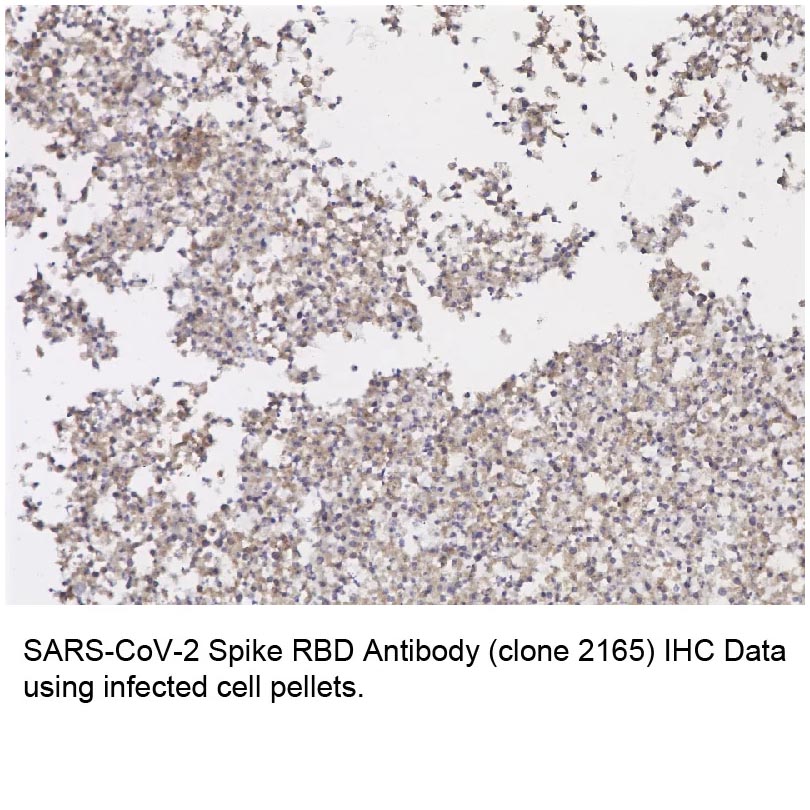

Immunohistochemistry (paraffin sections): Recommended dilution: 10 μg/ml; positive control: colon, kidney.